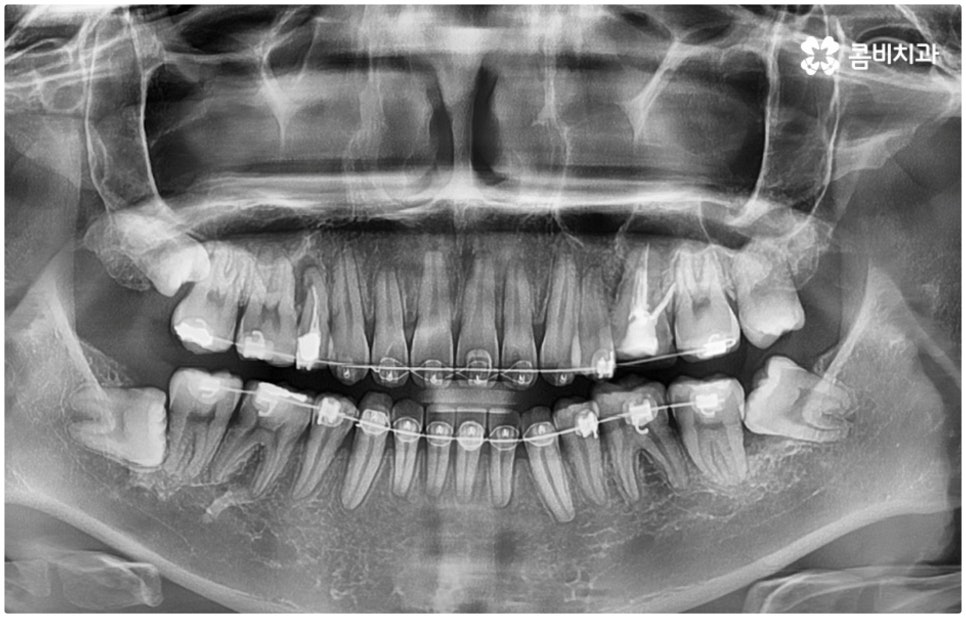

이와 같이 환자분들마다 상황에 맞게 사랑니 발치 시기를 결정하게 되는데 예를 들어 교정을 하는 분들이라면 사랑니를 언제 빼는 것이 맞을까요? 이 역시 검진을 꼼꼼하게 해 본 후에 결과에 따라 달라지게 될 텐데, 만약 아직 사랑니로 인해 충치와 같은 문제가 발생하지 않았고 부정교합 등에 영향을 주고 있지 않다면 교정을 하는 중간 혹은 교정이 끝난 다음 유지 장치를 하면서 적절한 시기에 발치해 주면 될 것이고 구강 질환이 생긴 상태라면 이를 먼저 치료한 다음 원인이 되는 사랑니를 발치한 후 차근차근 교정 치료를 진행하는 것이 좋을 거예요

이때 치과교정과 전문의 자격증과 통합치의학과 전문의 자격증을 동시에 갖추고 있으면서 경력 또한 풍부하신 담당의 선생님께 치료를 받으신다면 중간에 치과를 옮기실 필요 없이 필요한 처치를 제 때 받게되어 보다 편안하게 진료를 보실 수 있어요. 또한 발치를 할 때 무통 마취기 아이젝을 이용하는 매복사랑니발치치과 라면 환자분들의 불편과 통증을 좀 더 줄여줄 수 있으며 보다 안정적인 진료가 가능하니 이에 대해서도 한 번 체크해 보시길 권유드리고 있습니다.